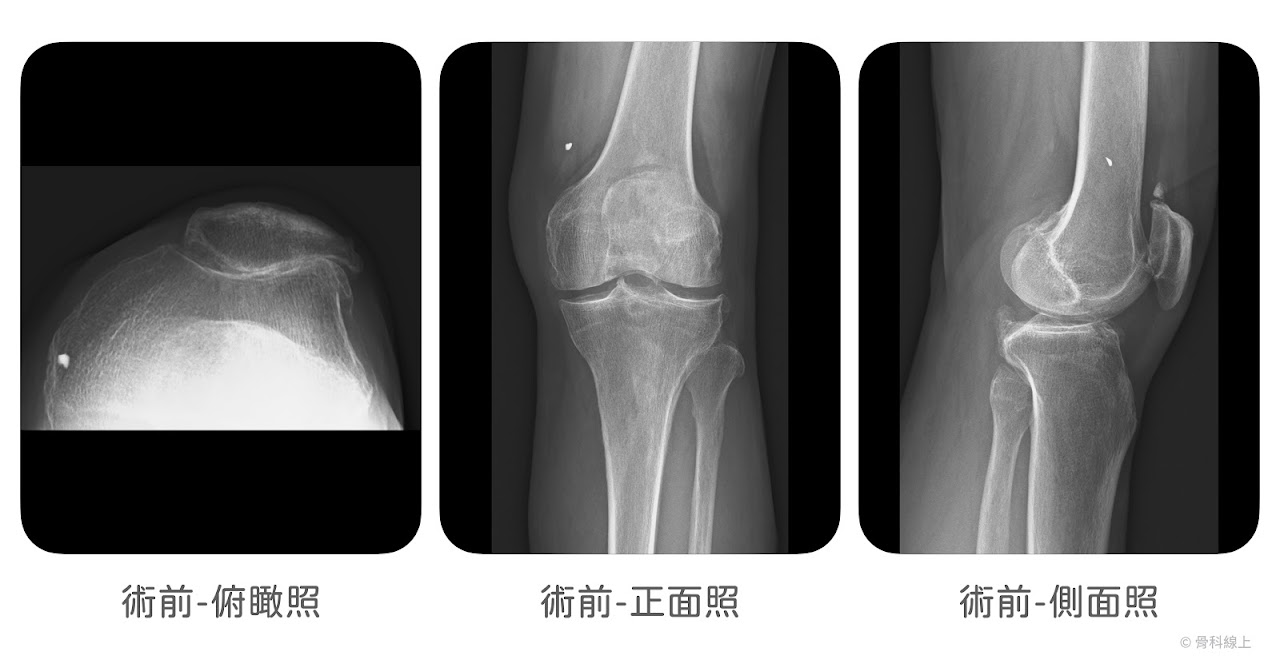

髕骨股骨人工關節置換手術

髕骨股骨人工關節,我們會說前方膝蓋骨的磨損,所以這樣的置換手術,不會處理內、外側關節面,也需符合幾個特定條件:

(1) 只有前方,髕骨股骨關節面的磨損

髕骨股骨關節面的磨損,常合併明顯的髕骨外翻或是脫位,所以髕骨股骨關節置換手術的概念,像是「重新鋪一個飛機跑道」讓髕骨可以穩穩的「降落」在軌道裡面,並且使表面光滑(resurfacing),緩解磨損症狀。

髕骨股骨人工膝關節置換手術過程示意圖